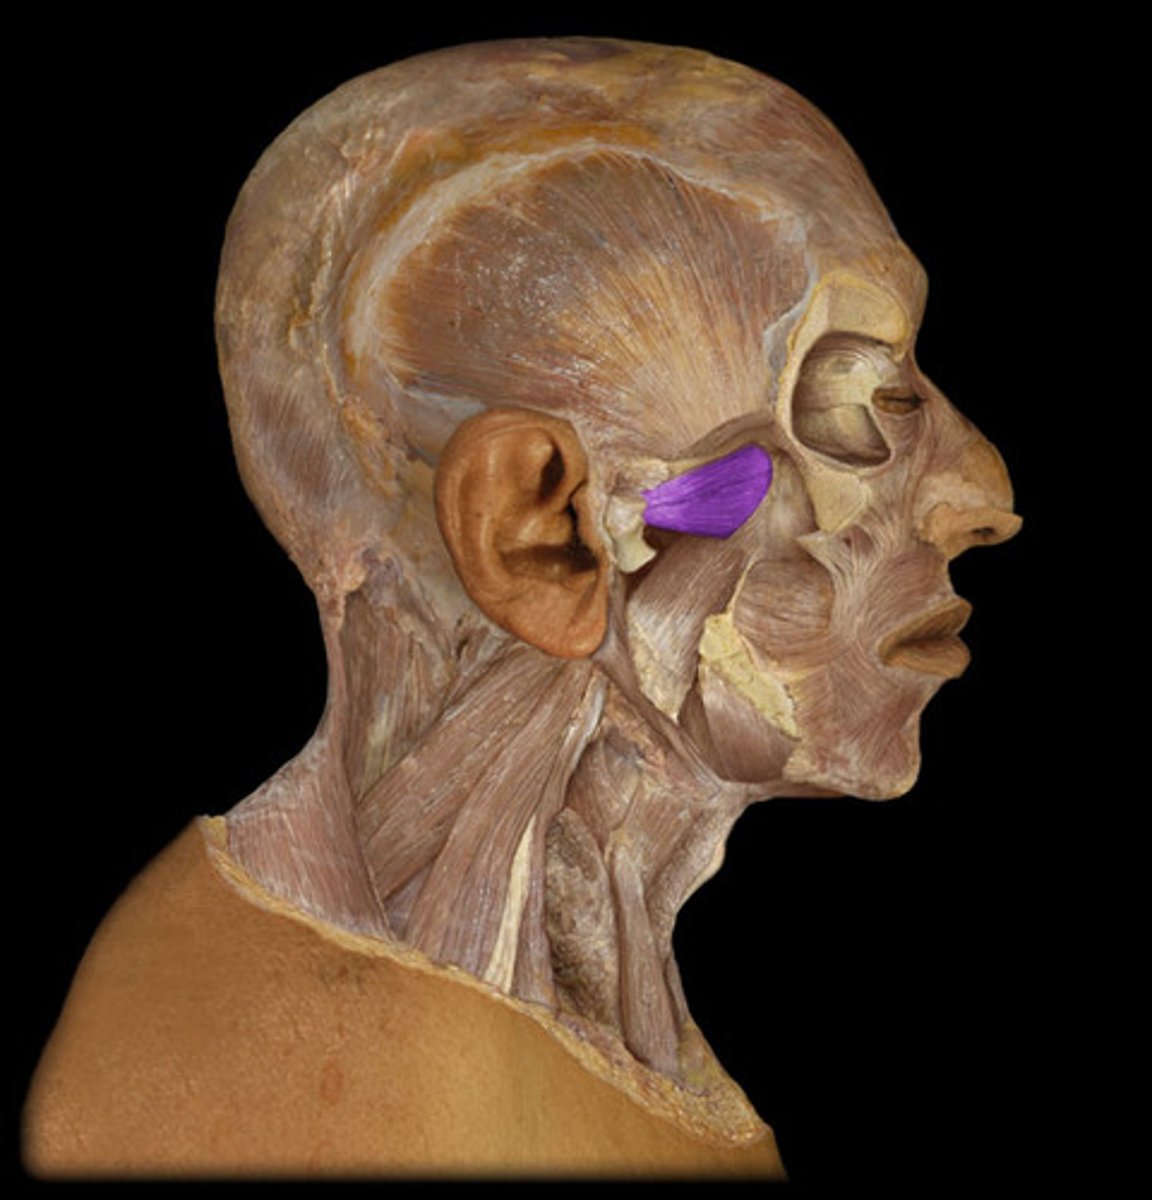

Temporalis